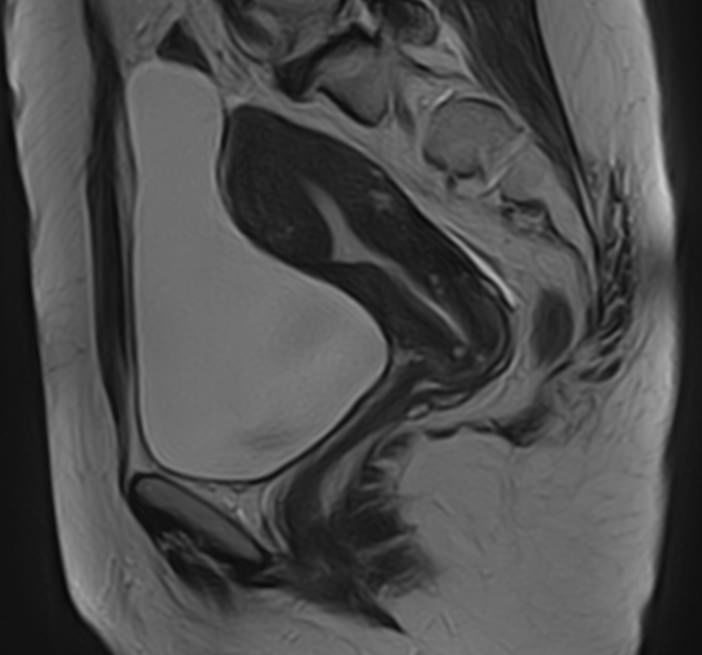

В клинике «Доступная медицина» магнитно-резонансная томография выполняется на высокопольном 32-канальном томографе последнего поколения TOSHIBA VANTAGE TITAN 1,5 Тесла, который обладает высокой разрешающей способностью и обеспечивает непревзойденное качество изображений. Аппарат производит сканирование в трех взаимоперпендикулярных плоскостях и послойными срезами с шагом от 1 мм, что позволяет визуализировать структуру органов и тканей малого таза в мельчайших подробностях. Точная и достоверная информация позволяет выявлять различные заболевания на начальной стадии, от чего напрямую зависит успех лечения.

С помощью данного исследования можно получить детальное послойное изображение матки, яичников, мочевого пузыря и мочеотводящих путей, а также жировой клетчатки, окружающей органы, и лимфатических узлов.

МРТ-сканирование органов малого таза позволяет выявить:

• Изменение формы и положения матки (двурогая матка, патологический загиб матки, гипоплазия);

• Миоматозные узлы, полипы и новообразования в матке;

С помощью МРТ стало возможным проведение бесконтрастной урографии, которая позволяет подробно исследовать мочевой пузырь и мочевыводящие пути. В отличие от сходного метода с применением рентгена МРТ урография исключает лучевую нагрузку и не требует введения контрастных веществ на основе йода, которые могут вызвать аллергию.